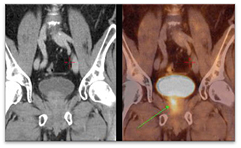

During the last decade the development of novel radiotracers provided PET a more relevant role in prostate imaging. The most widespread of these tracers are those based on choline labelled with different radioisotopes (Hara et al 1998, DeGrado et al 2001, Chen et al 2012). Choline is a compound that supports the synthesis of cell membranes and thus proliferation. In the case of prostate cancer, it has been strongly related with elevated levels of choline uptake and certain choline metabolites, which can be used as potential prognostic biomarkers for the management of prostate cancer patients (Awwad et al 2012). The Fluorocholine (FCH) molecule labelled with 18F showed the highest biological compatibility with choline leading to a behaviour in the body very similar to that of natural choline (Hara 2001). An example of carcinoma detection on 18F-FCH PET with bladder accumulation is shown on figure 1, where the tumour is pointed with an arrow. A well-known drawback of 18F-FCH and other 18F-based radiotracers is their variable urinary excretion with high accumulation in the bladder, which can affect detectability (Schoder and Larson 2004, Massaro et al 2012). Reported solutions in order to mitigate this effect are mainly aimed at early acquisitions or bladder voiding by urinary catheterization (Witney et al 2012), but these solutions are not ideal for several reasons. On the one hand, the accumulation of radiotracer in the bladder is a patient-dependent process so early acquisitions cannot guarantee avoiding bladder accumulation (Massaro et al 2012). On the other hand, catheterization for bladder voiding is an invasive process that has been identified as a potential source of infection (Lo et al 2014). Despite this serious shortcoming, 18F-FCH is currently the radiotracer of choice for prostate PET imaging with indications for diagnosis, staging, restaging, and therapy monitoring in prostate cancer (Hodolic 2011, Beheshti et al 2013, Chondrogiannis et al 2014). The usage of bladder voiding, early acquisitions or both is highly centre-dependent.

Figure 1. 18F-FCH PET/CT detects a metabolically active prostate carcinoma, pointed with an arrow. Image is reproduced with consent from Vivantes International Medicine (Am Nordgraben 2, Berlin, Germany).

Standard image High-resolution imageRegarding quantification, 18F-FCH PET images have shown high SUV variability in normal prostate tissue (SUV 3.4–4.1), prostate cancer (SUV 1.7–6.2), and local recurrence (SUV 2.7–12.42) (Tindall and Scardino 2011). The reasons for this variability are still unclear, since SUV can be affected by different factors. Verwer et al (2015) modelled the 18F-FCH-PET kinetics of lymphatic and haematogenous metastases and proposed modifications in the SUV calculations to address problems related with 18F-FCH-PET kinetic studies. In this context, additional work is required for evaluating technical issues related to acquisition, reconstruction, and quantification (Boellaard 2009, Adams et al 2010, Silva-Rodríguez et al 2015). Particularly important in 18F-FCH-PET imaging might be the overestimation due to the inclusion of spill-in counts originally coming from separated high-activity regions such as the bladder. This effect has been defined in the literature as spill-in (Bai et al 2013) or shine-through effect (Liu 2012) and included in a broader definition of the partial volume effect (PVE) by different authors (Soret et al 2007). This effect has been widely reported in cardiac SPECT (DePuey et al 2012), dual tracer parathyroid scintigraphy (Wu et al 2003, Liu et al 2005), and 18F-FDG PET (Liu 2012, Du et al 2013). In PET, different cases have been reported to affect the quantification of lung tumours when the lesions are in the vicinity of the myocardium or the quantification of prostate tumours close to the urinary bladder (figure 1). Despite multiple methodologies that have been proposed for the correction of the underestimation produced by the spill-out counts in small regions (Erlandsson et al 2012), which responds to the most traditional definition of PVE (Rousset et al 1998), the effect of spill-in counts has been less studied and it is not routinely corrected for in PET studies.